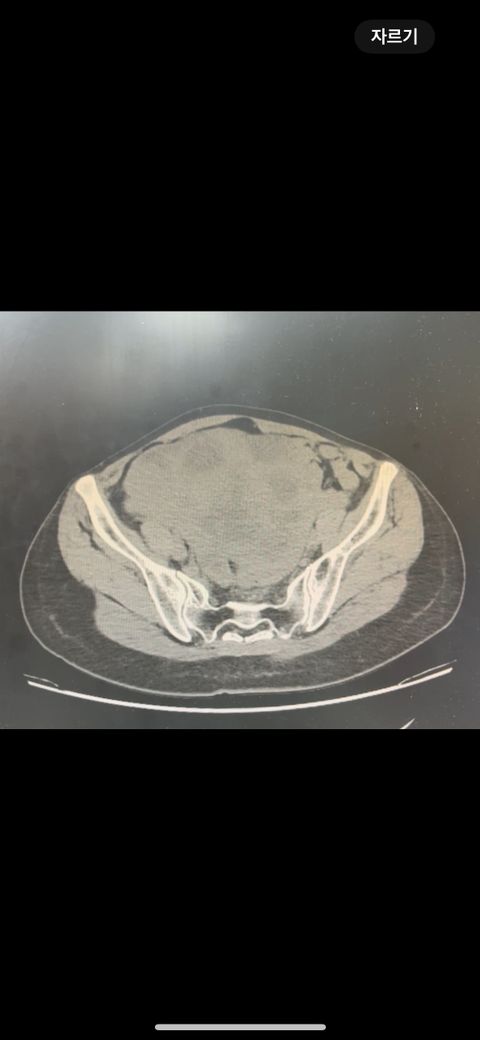

복부 ct 판독 부탁드립니다 (contrast)

결과는 3일 뒤 보긴 하는데 우선 영상만 있는 상태라 영상 캡쳐 한 거 대략적으로라도 확인해주실 수 있나요.. !!!!!!!!!!

• 3번 째 사진

*** 먼저 답변드리기에 앞서 상기 질문에 대한 답변은 굉장히 제한된 답변이고, 경우에 따라 틀린 답변이 될 수 있습니다. CT의 경우 단면을 연속적으로 봐야 의학적인 설명이 가능하기 때문에 일부 사진만으로는 해석이 어려울 수 있습니다.

위 사진에서는 비장비대의 가능성과 자궁쪽으로 혹이 일부 보이는 소견이 의심되나, 정확한 판독은 3일 뒤에 받아보시는 것이 도움이 될 수 있겠습니다.